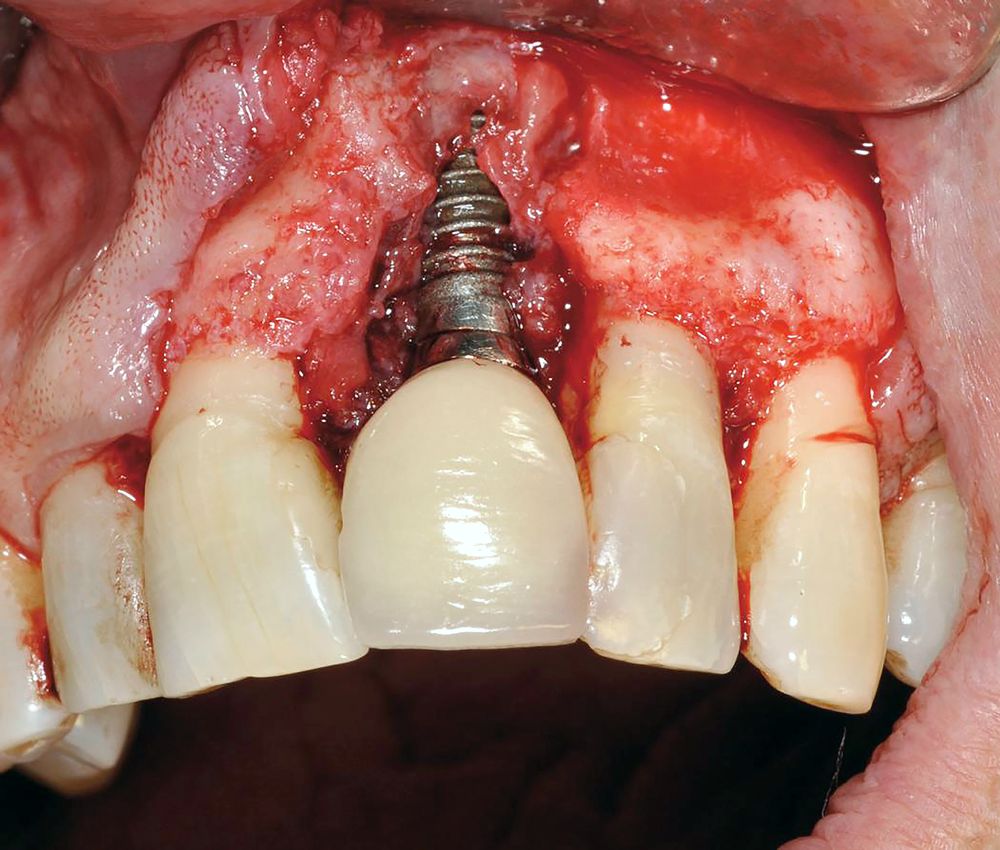

Una de ellas es la periimplantitis apical (PIA), entidad descrita en los años 901 como un proceso infeccioso-inflamatorio de los tejidos que rodean al ápice de un implante dentario integrado.

La PIA tiene como elemento central la falta de osteointegración únicamente en la zona apical del implante. En una revisión bibliográfica del 2011, Romanos et al. afirman que, a pesar de las técnicas diagnósticas disponibles, hoy en día no es posible establecer si la PIA representa una cicatriz ósea, una nueva lesión destructiva del hueso alveolar o una reactivación de una lesión previa.